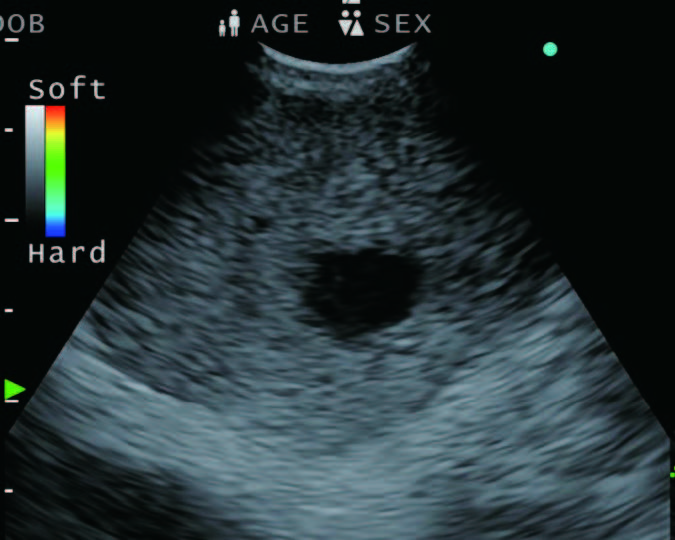

Elastography

Figure 4 - The side-by-side B-mode and i-ELST allows us to target the appropriate areas within the lesion in real time.

Elastography is a recent addition that can assess the hardness of the lymph node during EBUS. There is a theoretical advantage when one can assess the nature of the node before sampling it and to decide whether sampling would be useful, and even better if there are different areas of the nodes that need to be sampled to improve the outcome of the puncture. While the previous version of this processor had this capability, the EU-ME3 is newly equipped with “i-ELST” mode, that enables stable ELST images even with weak pulsation. The option of being able to view a B-mode and Elastography or Doppler in the same frame as adjacent pictures (see Figure 4) helps us target the desired area of interest in the node.